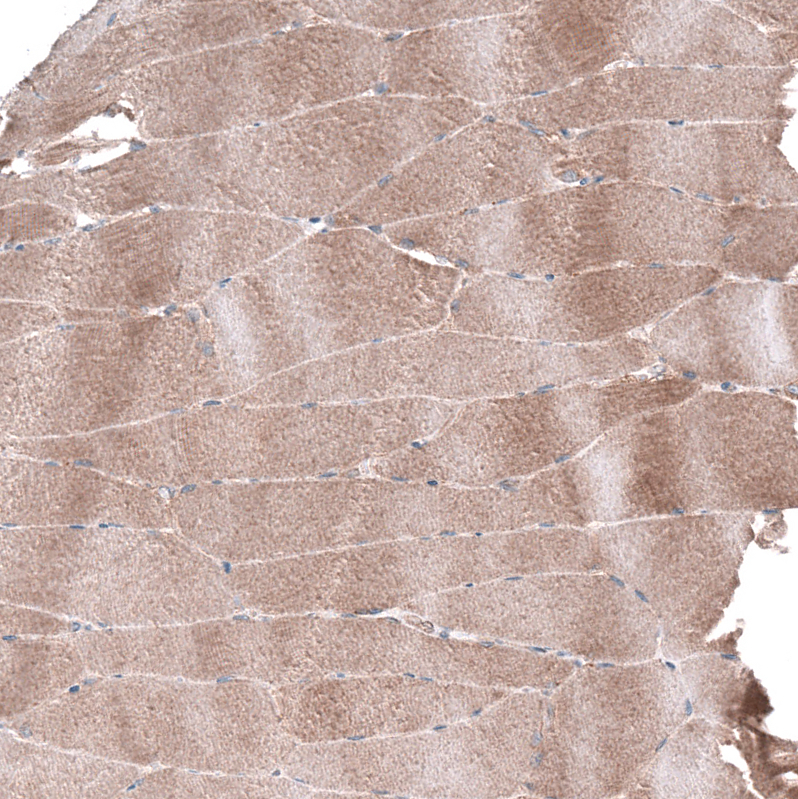

Immunohistochemical staining of human skeletal muscle shows strong cytoplasmic positivity in myocytes.